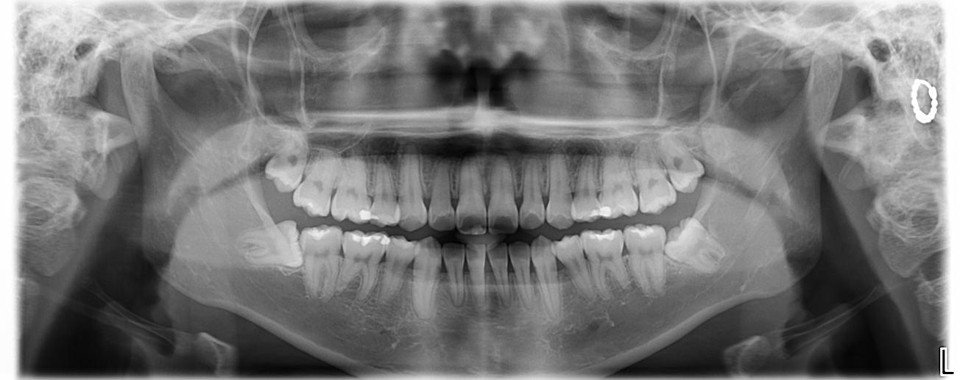

治療前,環口X光,深度蛀牙